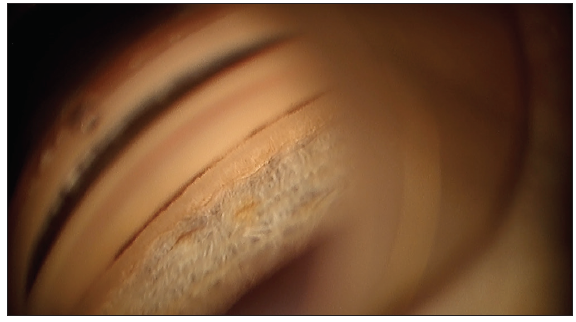

Figure 2. View of the angle, depicting the ciliary body band (CBB), the suprachoroidal space (SS), and the trabecular meshwork (TM).

With this procedure, the key is to achieve an en face view (Figure 3). If the surgeon views the trabecular meshwork (TM) through the gonioprism but it is pointing downward, then he or she should tilt the patient's head and/or the microscope until the TM is pointing at the surgeon. This will ensure the best angle to engage the TM.